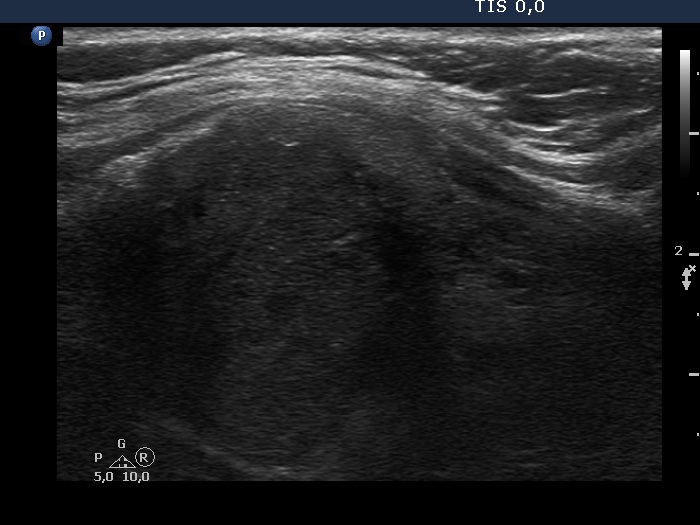

TIRADS - case 1147

Follow-up examination six years after the first visit (ultrasonographic picture 7)

Upper part of the left lobe, longitudinal scan. The echogenicity of the nodule has decreased.